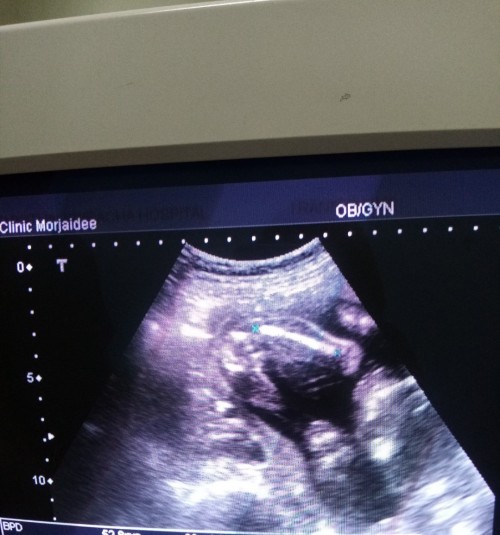

บ้านนี้ลุงหมอบอกว่าได้ลูกสาวจ้า แม่ๆ ได้เพศไหนกันบ้าง #ทีมมกราคม65 #ขอบคุณสำหรับคำตอบค่ะ #ใครมีประสบการณ์